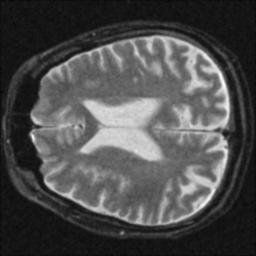

After analyzing the images, the following table was determined:

The resolution loss is measured relative to the FWHM of the noisy image, consequently its resolution loss is 0%. Interesting is that the CNR mirrors changes in the SNR, as expected. Also interesting is that the contrast filter reduced the SNR dramatically while actually improving the image resolution. The following images were obtained after filtering:

Noisy Image

Correlation Filter

Wiener Filter

Median Filter

Average Filter

Contrast Filter

Gaussian Filter